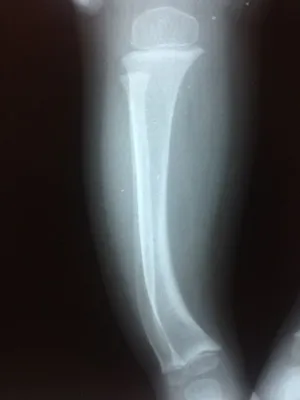

Xrays of Bow Legs in toddler (Below)

Knock knee position is demonstrated (left), and the bowleg position is also pictured (right).